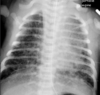

Meconium Aspiration

Term babies

Hyperinflation (ball-valve –> air trapping)

Coarse, Reticular, Ropy asymmetric perihilar opacities

NO AIR BRONCHOGRAMS

Risk of PTX

Mortality from severe CLD and Pulm HTN